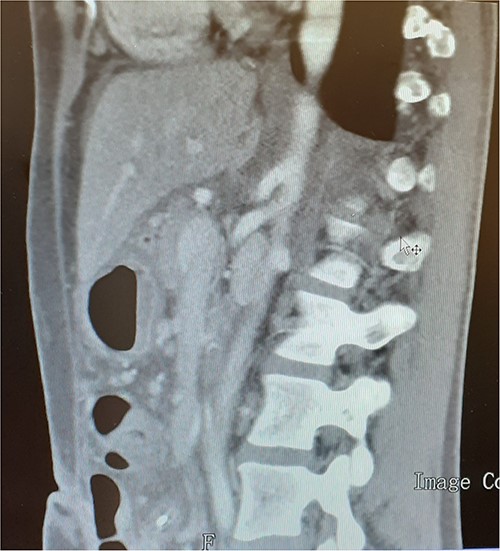

A 37-year-old woman with autoimmune thyroiditis, epilepsy, anti-erythrocyte S antibody and with suspected mixed cryoglobulinemia under study was evaluated for recurrent postprandial abdominal pain with 6 months of evolution, fullness and vomiting with copious meals and weight loss of about 7 kg in 6 months, having already performed a computed tomography angiography (CTA) that revealed MALS (Fig.1). In collaboration with the General Surgery Department, a section of the MAL and lysis of the adhesions by laparoscopic approach was performed. On the third postoperative day, the patient developed a chylous fistula that resolved with conservative strategy including oral diet discontinuation, parenteral nutrition and octreotide. At 1 year follow-up, the patient showed clinical improvement in abdominal pain and food tolerance, and imagiological improvement (Fig.2).